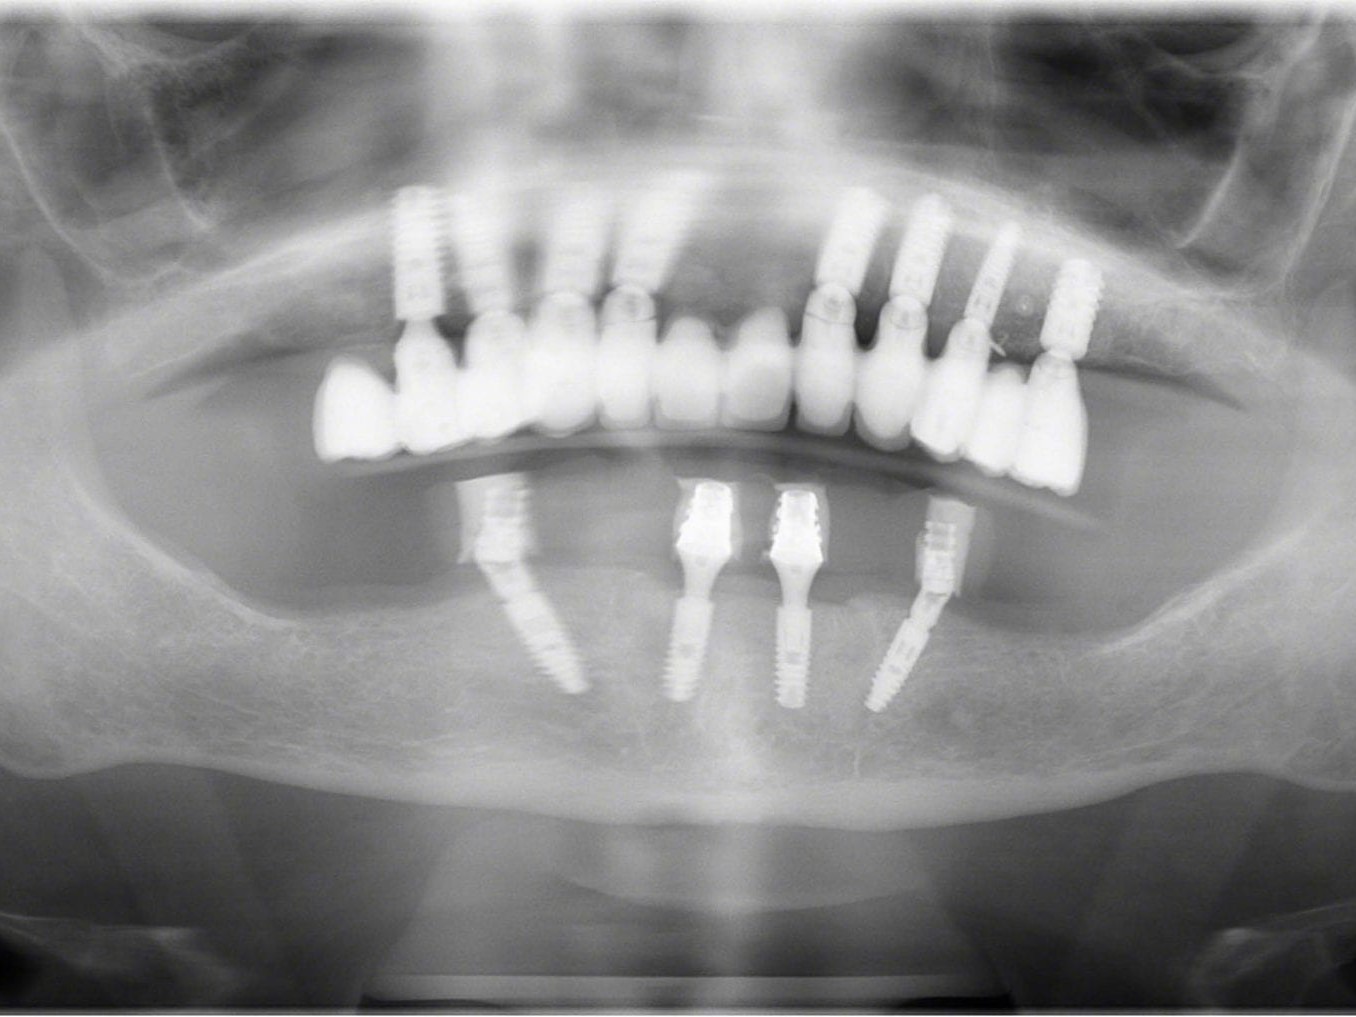

Bei dem nachfolgenden Fall handelt es sich um eine 74-jährige Patientin, die nicht raucht sowie im guten Allgemein- und Ernährungszustand ist. Sie steht in keiner medikamentösen Behandlung und hat keine Allergien. Erstmals kam die Patientin 2006 in die Behandlung der Autoren. Damals zeigte diese eine insuffiziente Teleskoparbeit im Oberkiefer, wobei die Pfeilerzähne einen deutlichen Lockerungsgrad aufwiesen. 2006 wurde der Oberkiefer mit acht Ankylos® Plus Implantaten (Dentsply Implants, Mannheim) und einer Sofortversorgung bei gleichzeitig durchgeführtem Sinuslift rehabilitiert. Acht Monate später erfolgte die endgültige prothetische Versorgung in Form einer festen Verblendkeramikauf NEM-Gerüst unter Verwendung von Titan-Abutments. Seit dieser Behandlung ist die Patientin in einem regelmäßigen Prophylaxe-Programm eingebunden und zeigt eine sehr gute Mundhygiene. Die seinerzeit belassene Unterkieferprothetik war mittlerweile insuffizient. Es konnten im Unterkiefer keine Zähne erhalten werden. Seitens der Patientin bestand der Wunsch nach hochwertiger Rehabilitation des Unterkiefers möglichst mit einer Sofortversorgung. Eine zwischenzeitliche Versorgung mit einer gingivagetragenen Interimsprothese schied aus. Darüber hinaus war für die Patientin wichtig, eine möglichst geringe Belastung durch die anstehende Behandlung zu erfahren. Es fiel die Wahl auf die prothetische Lösung mit anguliert gesetzten Ankylos® C/X-Implantaten nach dem SmartFix-Konzept (Dentsply Implants, Mannheim), ein implantatprothetisches Verfahren zur Sofortversorgung von zahnlosen Patienten mit verschraubten Brücken im Unterkiefer. Die Patientin wurde mit einem computerdesignten Langzeitprovisorium über 4 Monate versorgt (Abb. 1).

Wie weiter oben bereits beschrieben ist die Patientin im Oberkiefer mit einer keramisch verblendeten implantatgetragenen Brücke versorgt. Aus Sicht des Behandlungsteams schied daher eine keramische Verblendung des Unterkiefers aus. Die Verwendung von einem Composite mit keramischer Füllstruktur gewährleistet neben der notwendigen Farbstabilität und Plaqueresistenz zwei weitere Vorteile. Auf der einen Seite entsteht im Okklusionsmoment nicht das „keramische Klacken“ und zum anderen werden die auftretenden Kaukräfte gleichmäßiger auf das Implantat und den Knochen verteilt . Gerade bei implantologischen Oberkiefer- und Unterkieferversorgungen ist dieser „Stoßdämpfer–Effekt“ für den Langzeiterfolg wichtig. In dem vorliegenden Fall wurde die okklusal verschraubte Brücke aus einem massiven Titanblock gefräst (Abb. 4 und 5), wodurch das Endprodukt frei von aus der Gusstechnik bekannten Lunkern oder Verzügen ist. In Übereinstimmung mit den als Sheffield-Test ⁷ bekannten Kriterien der University of Sheffield, GB. ermöglicht dieser Fertigungsprozess gepaart mit der verblockten Abdrucknahme einen präzisen und somit spannungsfreien Sitz der Brücke – sowohl auf dem Meistermodell als auch im Munde des Patienten. Sowohl die Verblendungen der Zähne als auch des Zahnfleisches wurden unter Zuhilfenahme der diagnostischen Aufstellung mit visio.lign ⁸ im Labor angefertigt. Hierbei wurde besonderer Wert auf die naturgetreue Nachbildung der Rot-Weiß-Ästhetik und eine gute Hygienefähigkeit gelegt. Die Vorteile dieses Verblendsystems liegen in der exakten Umsetzung von der Aufstellung hin zur fertigen Arbeit durch mehrschichtige Verblendschalen (Abb. 6). Diese Verblendschalen werden schon bei der diagnostischen Aufstellung individualisiert und nach der Gerüstfertigstellung weiterverarbeitet. Mit passenden Individualisierungs- und Ergänzungsmassen sowie einem farblich abgestimmten Verbundsystem mit sehr guter Druck-Scheer-Festigkeit ⁹ ermöglicht dieses System durch Hinterlegen mit Intensivfarben das Gestalten von Mamelons ebenso wie die individuelle Gestaltung von Dentinleisten. (Abb. 7 und 8). Nach der zahntechnischen Erstellung der Unterkieferbrücke wurde diese intraoral inkorporiert (Abb. 9a). Die Implantatschrauben wurden mit 25 Ncm angezogen. Ein wichtiger Hinweis ist, dass hier stets das Originalequipment des Herstellers oder ein elektronisch kalibrierter Schraubendreher seine Anwendung finden sollte. Die Schraubenkamine wurden initial mit einem bakteriendichten, formstabilen lichthärtenden temporären Füllungsmaterial ¹⁰ verschlossen (Abb. 9b). Nach 6 Wochen werden die Implantatschrauben seitens des Prothetikers nochmals kontrolliert und ein abschließendes OPG erstellt (Abb. 10).